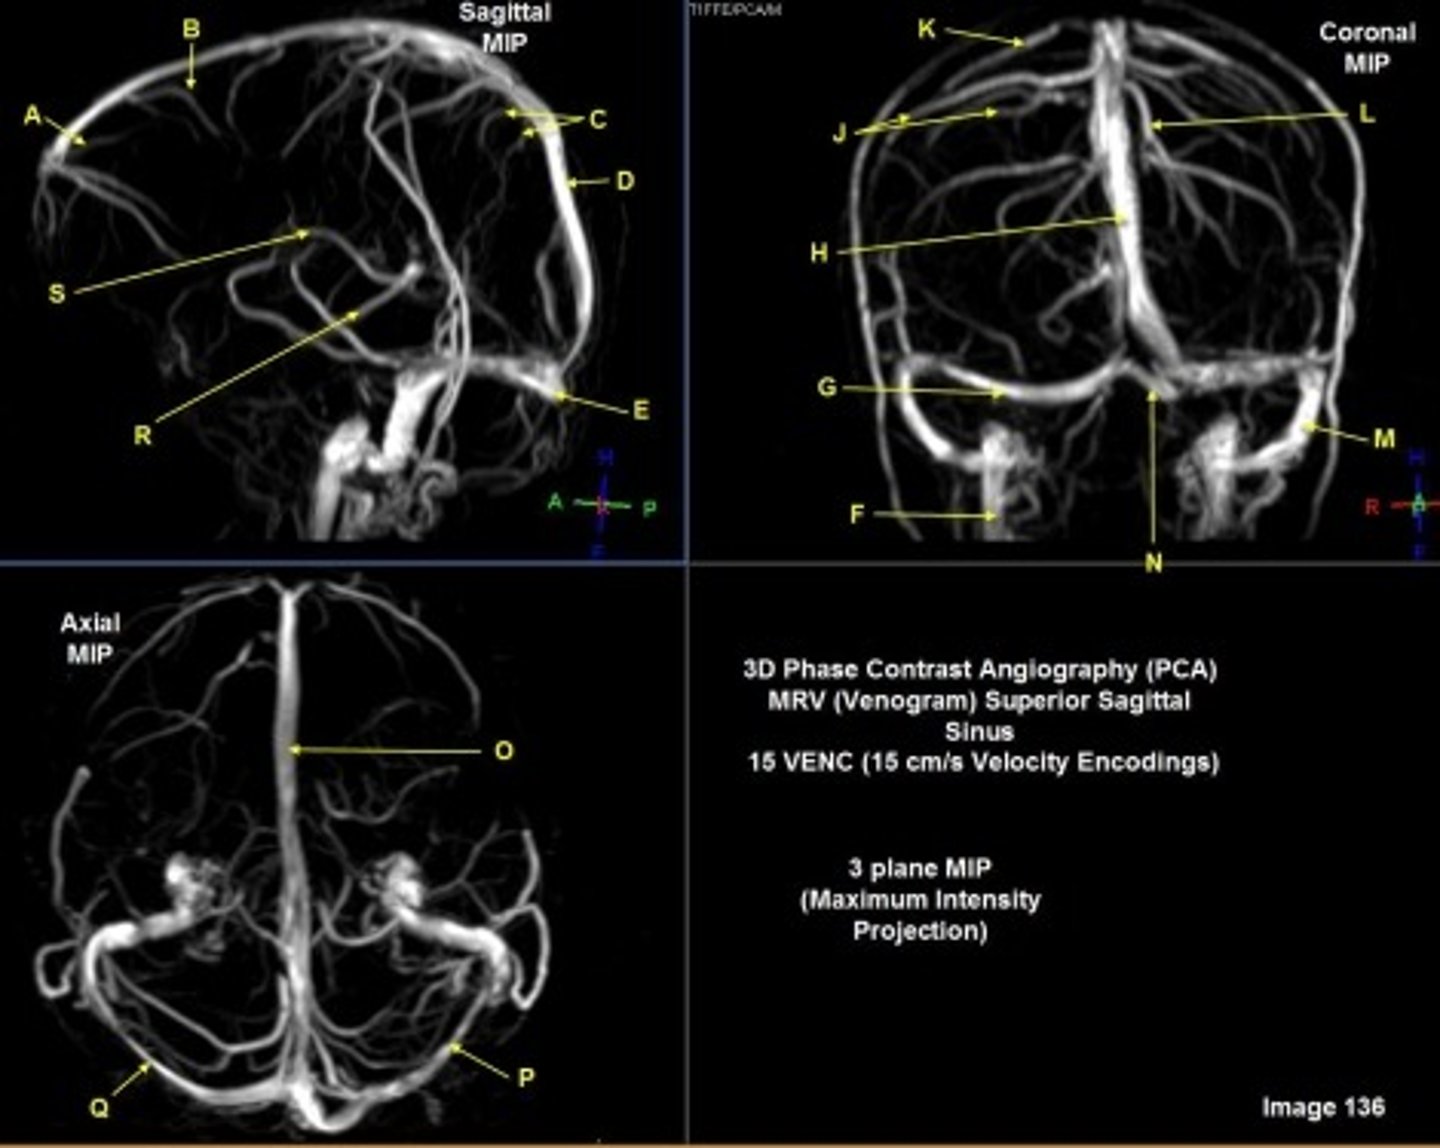

What type of sequence?

T2 FLAIR; Sagittal

A FLAIR (Fluid Attenuated Inversion Recovery) sequence is utilized to suppress signal from cerebrospinal fluid (CSF).

A

lateral ventricle

B

corpus callosum

C

thalamus

D- separates what

tentorium cerebelli- cerebrum (occipital and temporal lobes) from brainstem and cerebellum

E

fourth ventricle

F

medulla oblongata

Internal carotid artery

Caudate nucleus

white matter

D

straight sinus

G

H

lateral sulcus

L

optic chiasm

O

Splenium of corpus callosum

V

Cerebral peduncle

W

superior sagittal sinus

X

vein of galen

Y

Inferior colliculus of midbrain,

just inferior to pineal gland / superior to the cerebral aqueduct

Letter N in Image 137 is pointing to what type of tissue?

The corpus callosum is the only white matter tissue structure found in the midline sagittal slice of the brain.